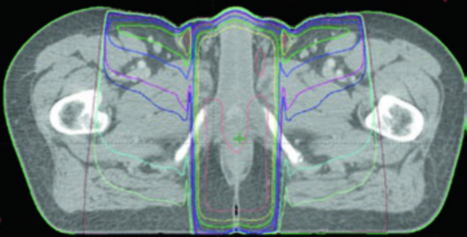

The T2N0 case demonstrates definitive chemoradiotherapy with IMRT: PTV-LR and PTV-HR treated simultaneously to 40 Gy (1.6 Gy/fraction) and 45 Gy (1.8 Gy/fraction) in 25 fractions, respectively. Then PTV-P received a sequential boost to 50.4 Gy (1.8 Gy/fraction) in 28 total fractions.

The T3N1a case with bilateral inguinal involvement had PTV-LR and PTV-HR treated simultaneously to 40 Gy and 45 Gy in 25 fractions. The bilateral inguinal and external iliac nodes were included in CTV-HR due to bilateral inguinal involvement. PTV-P and PTV-N then received a sequential boost to 54 Gy in 30 total fractions.

| CTV-HR (high risk) | Covers CTV-P, CTV-N, entire mesorectum, perirectal nodes, and bilateral internal iliac nodes inferior to the inferior border of the sacroiliac joint. If inguinal or external iliac nodes are involved, include these regions. 0.7 cm margin around internal iliac vessels. 1.8 cm strip between external and internal iliac vessels for obturator nodes. 1–1.5 cm anteriorly into bladder |

| CTV-LR (low risk) | Covers uninvolved internal iliac nodes superior to the sacroiliac joint inferior border, plus uninvolved external iliac and inguinal nodes. Margins: 0.7 cm around internal iliac vessels; 1 cm anterolateral on external iliacs; entire inguinal compartment contoured |

| PTV | 0.5–1 cm expansion from each CTV, depending on setup accuracy, imaging frequency, and IGRT use |